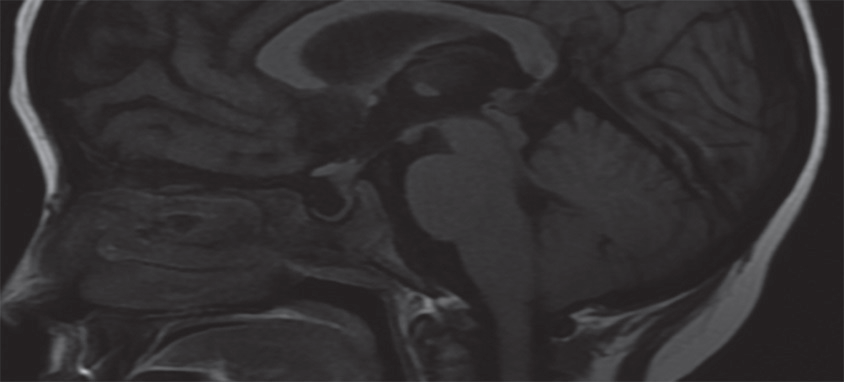

Cortes en secuencia T1 de resonancia magnética con gadolinio que muestran aumento de tamaño de los plexos coroideos, con reforzamiento moderado. En la exploración dirigida a órbitas se logra identificar compromiso del ala menor del esfenoides derecho.

Reconstrucción sagital en secuencia FLAIR de resonancia magnética que muestra ocupación de silla turca por líquido cefalorraquídeo que desplaza en sentido posterior la glándula hipófisis.